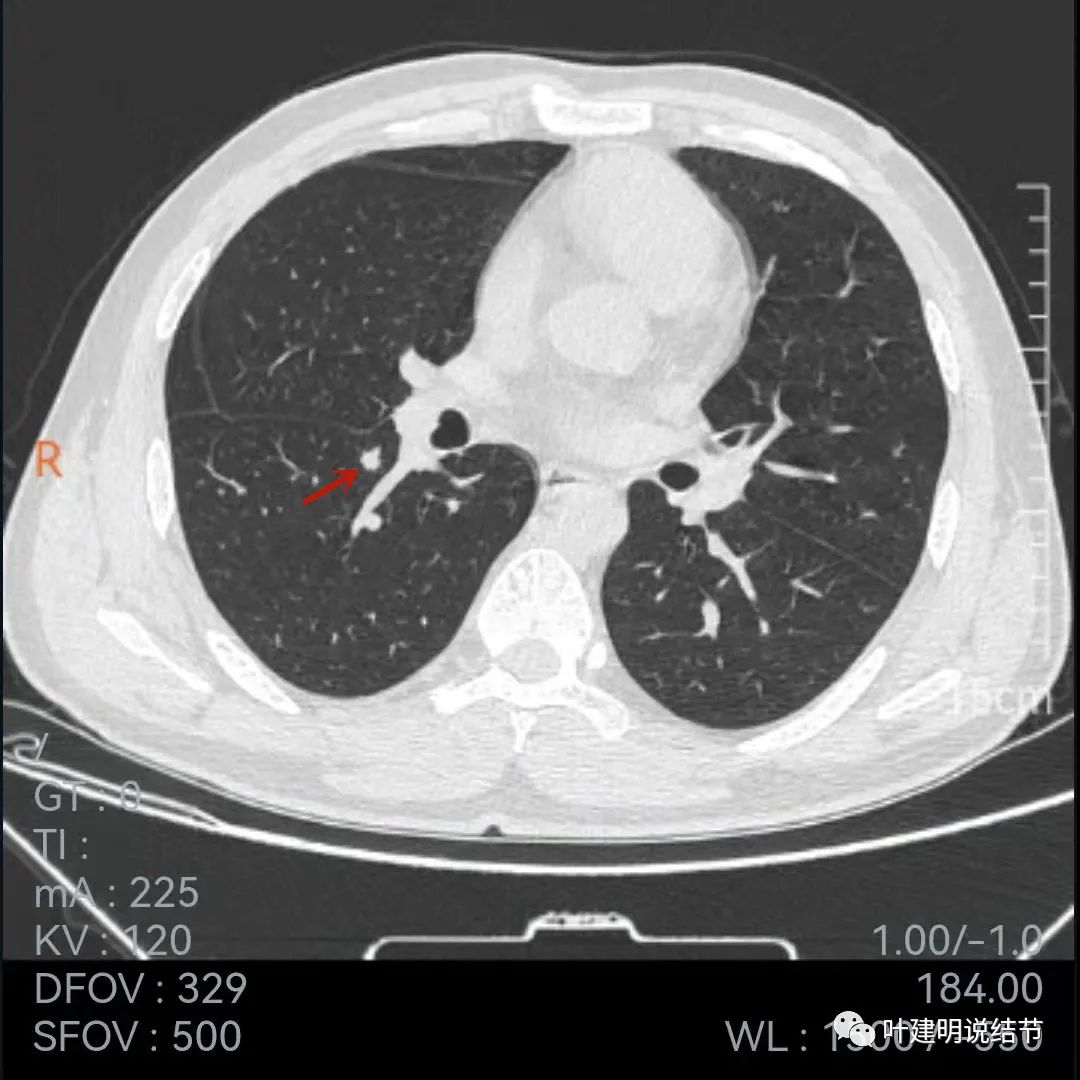

再看下面2020年7月的平扫片子:

非薄层的看,病灶还是小结节,实性,边缘似乎比前一年略有毛糙,胸膜轻微牵拉,黄色箭头所指似乎病灶中央的密度比周围部分略低,会不会是肉芽肿性炎伴有少许坏死?